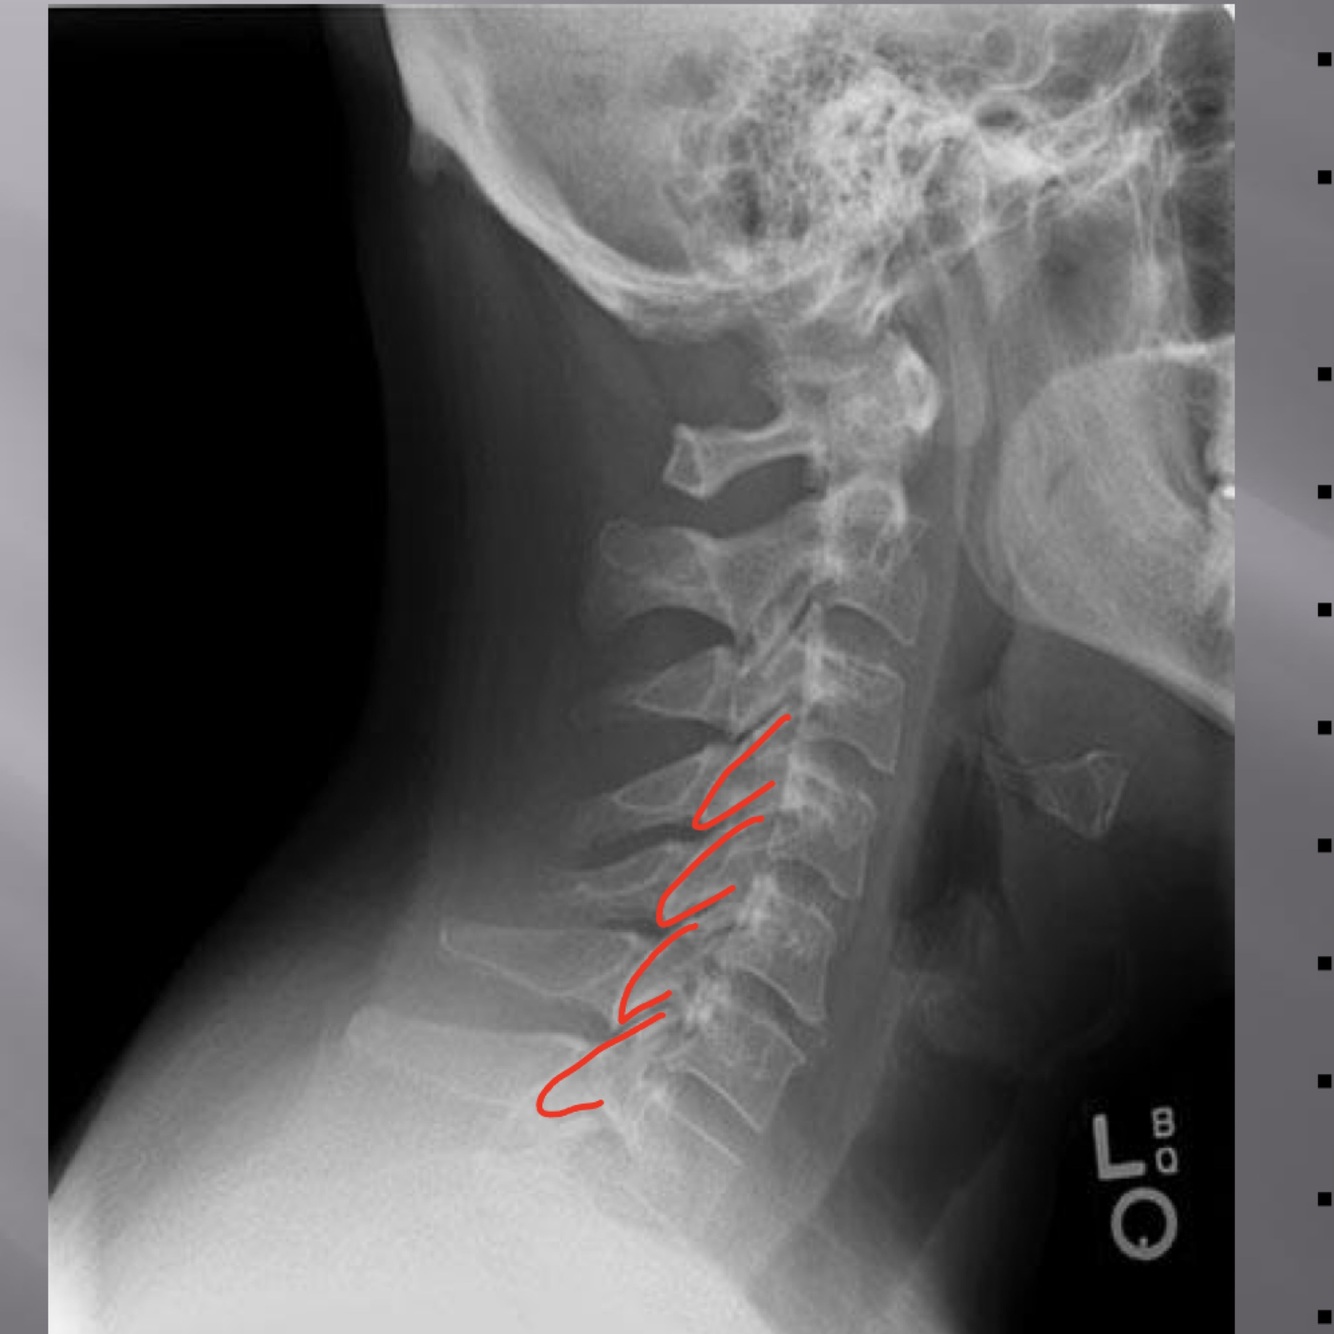

LATERAL CERVICAL LANDMARKS lateral cervical view

external acoustic meatus

Lateral cervical view

mastoid process (air cells)

posterior tubercle of c1

angle of mandible

EOP

spinous process C2-C7

dens

posterior arch of C1

vertebral body c2-c7

rami of mandible

body of mandible

anterior tubercle c1

zygapophyseal joints

petrous portion

occipital condyle

Lateral cervical

superior endplate tips

inferior endplate tips

disc spaces

atlanto-dental interspace

hyoid bone